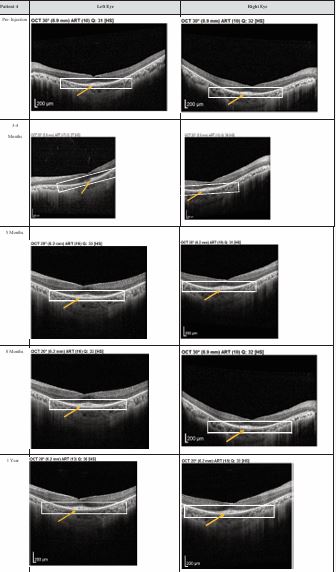

Figure 3 Optical coherence tomography (OCT) images for both eyes of Patient 3 from pre-injection up to 1 year follow-up. Orange arrow demonstrates the presence of hyperreflective material at the interdigitation area of the photoreceptors at the macula and extramacular region. These were observed and maintained until the last follow-up examination.

Figure 4 Optical coherence tomography (OCT) images for both eyes of Patient 4 from pre-injection up to 1 year follow-up. Orange arrow demonstrates the presence of hyperreflective material at the interdigitation area of the photoreceptors at the macula and extramacular region. These were observed and maintained until the last follow-up examination.